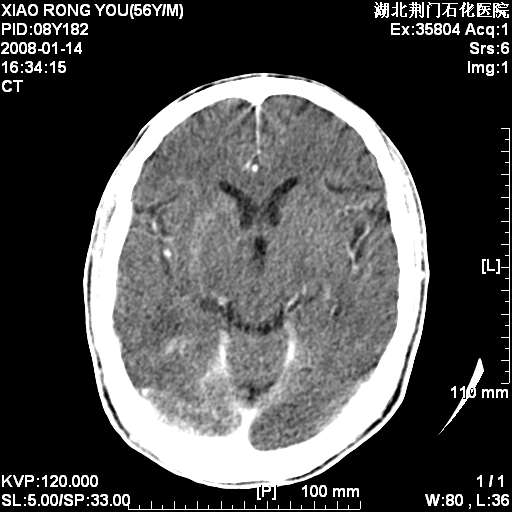

3天后增强

增强明显强化,转移?

如此血管样强化表现,转移瘤不好解释,考虑脑膜瘤或血管瘤

平扫无明显占位及水肿、增强扫描强化明显以血管瘤可能性大